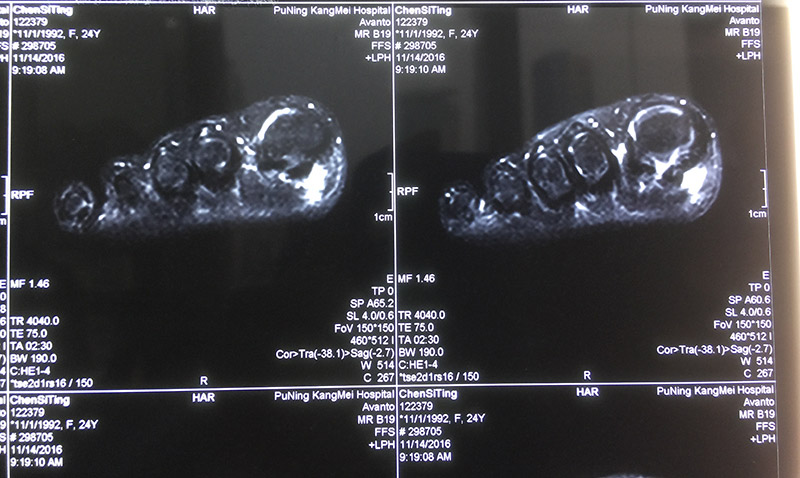

11月7日前往当地某中医院住院治疗,院内行右足脚趾MR提示:局部软组织水肿,血沉、血常规、C反应蛋白均提示无明显异常,医生给的诊断是肌腱炎,于是又继续抗感染治疗6天,陈小姐依然还是感觉大趾底部刺痛,行动不便。